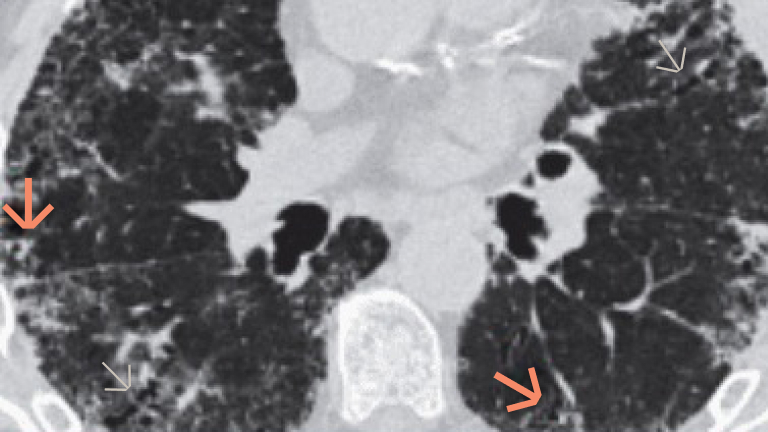

The pathogenesis of fibrotic interstitial lung disease in connective tissue diseases involves a complex interplay of inflammatory and fibrotic processes. Patients with connective tissue diseases (CTDs), such as rheumatoid arthritis, systemic sclerosis and primary Sjogren’s syndrome, develop fibrotic interstitial lung disease (ILD) via common pathogenic processes, irrespective of the underlying diagnosis or trigger. Fibrotic ILD often develops early in the course of a CTD. For example, in a study of systemic sclerosis patients, approximately 24% of systemic sclerosis-associated ILD patients showed an extent of more than 10% pulmonary fibrosis on high-resolution computed tomography at their baseline systemic sclerosis diagnosis. At the cellular level, ILD in CTDs is triggered by repeated tissue injury which induces an inflammatory response, and releases probiotic mediators, including VEGF, PDGF and FGF. These contribute to the recruitment and activation of leukocytes and fibroblasts. Resulting in a complex interplay of inflammatory and fibrotic processes. Activation of leukocytes also produces profibrotic mediators leading to further activation of the fibrotic process with excessive secretion of extracellular matrix. Excess extracellular matrix increases lung tissue stiffness, further activating fibroblasts in a feed-forward loop of self-sustaining progressive pulmonary fibrosis. Pulmonary fibrosis causes irreversible destruction and architectural disruption of the lung tissue. Based on the pathogenesis of fibrotic interstitial lung disease in connective tissue diseases, a new treatment paradigm of CTD-ILDs suggests to not only target inflammation but also fibrosis.

Zwłóknienie może obejmować już ≥10% objętości płuc pacjenta z CTD w chwili rozpoznania ILD17,18